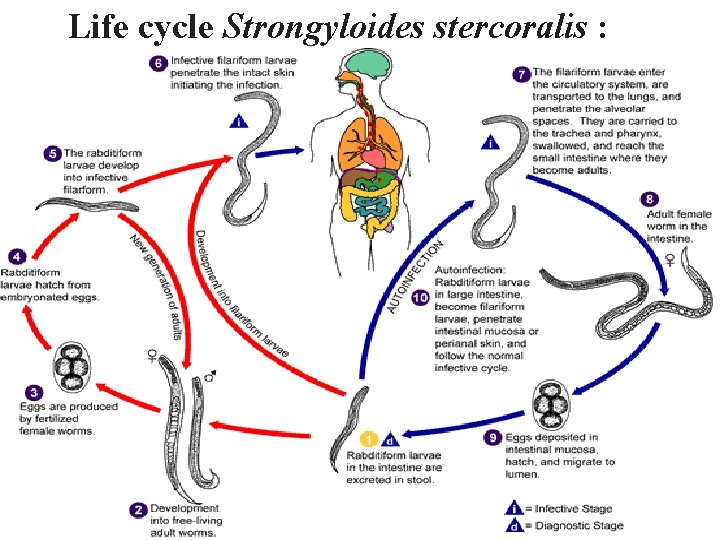

Life cycle Strongyloides stercoralis :